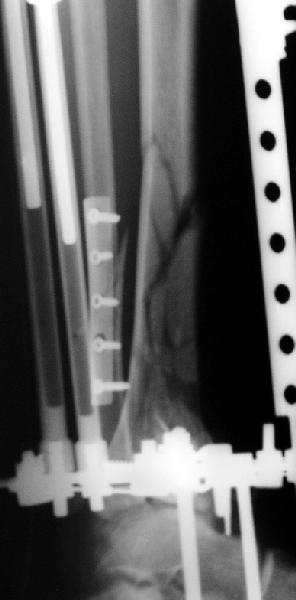

Смирнов Алексей 20 Март 2006, 23:49

Мне кажется, что все дискутирующие согласным с одним - надо воостанавливать в данной ситуации суставную поверхность. Сделать это закрыто (когда суставная поверхность состит из 3-фрагментов)лично для меня не реально. Конечно можно открыто отрепонировать, зафиксировать спицами и оставить в аппарате, но роль аппарата и выполняет LSP. Разрез в области внутренней поверхность голеностопного сустава и небольшой разрез в ср/3 голени для проксимальных винтов, надкостница не обдирается, пластина вводится подкожно.

Вид конечности на следующий день после операции.

Отправитель: Alexey Smirnov 27 Март 2006, 21:52

Наверно не дошел, вот еще раз.

8.jpg

14KB (14977 bytes)